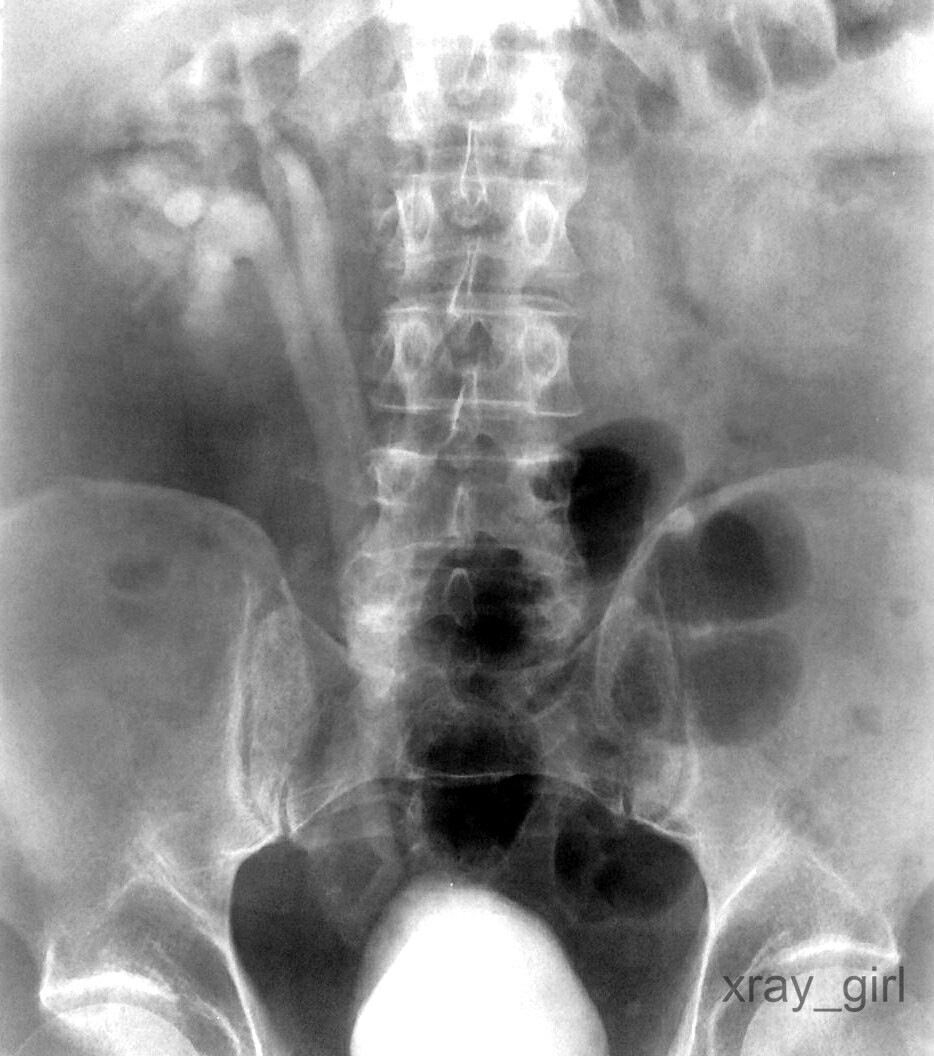

Radiography ˈRēnl ; Kidney Examination-AP.

The case below is doubling the right kidney. According to my analysis this is a rare and unique case, it may happen to anyone.

A rare and rare case but may occur and befall anyone for humans. Thank you @hilmicorel, and you have successfully completed a good task today.